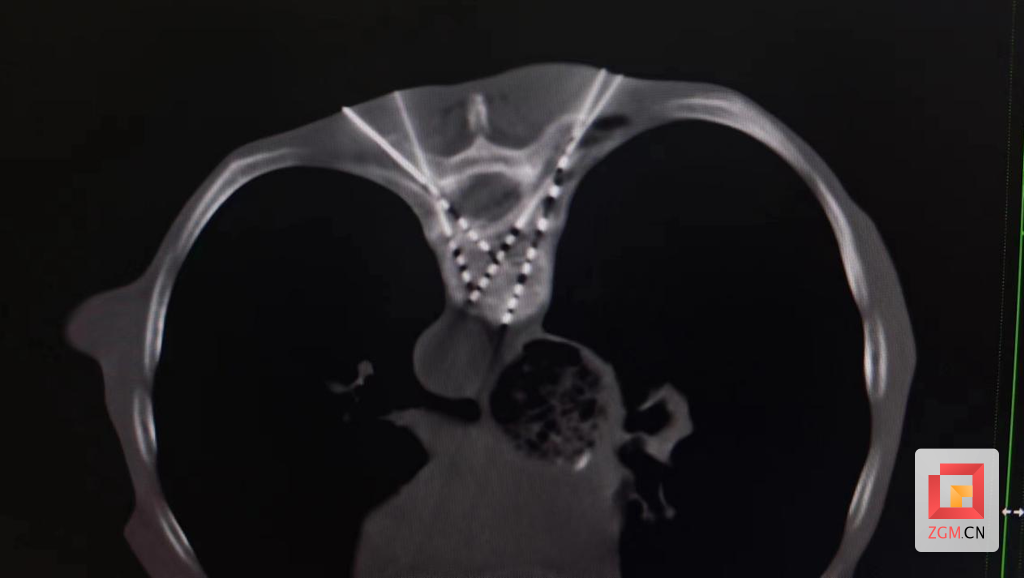

放射性粒子是将放射性同位素125碘吸附在银棒上外裹钛金属壳制成直径为0.8mm长度为4.5mm的钛金属微粒(称粒子),在三维治疗计划的引导下,通过植入针将粒子永久性植入肿瘤内,粒子持续释放低能量γ射线,可持续有效地杀灭肿瘤细胞,是目前治疗中晚期肿瘤的有效方法。

1、粒子准确植入肿瘤中,定位准确,靶向性强,高度适形。

1、粒子植入术为微创手术,不需开刀,用“牙签粗细”的穿刺针穿刺肿瘤,将粒子通过植入枪、植入针植入肿瘤,粒子不必取出,并发症少。